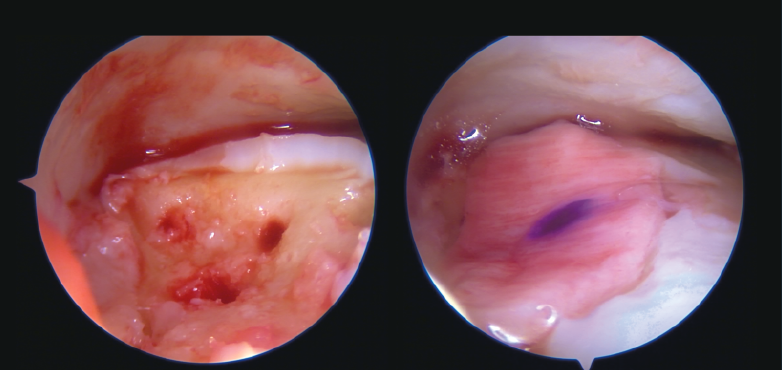

Figura 4. Lesión osteocondral en paciente con inestabilidad crónica de tobillo. Reparación directa, perforaciones y malla de condrocitos por vía artroscópica.

- Cirugía artroscópica: lesiones osteocondrales, tratamiento artroscópico de la inestabilidad (reparación y técnicas de reconstrucción), endoscopia posterior de tobillo y tendoscopia (Figuras 4, 5, 6 y 7).